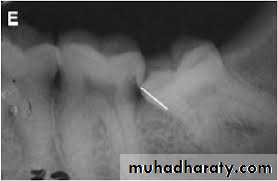

Periapical radiograph offers the highest definition and it should be used whenever possible, but the film should be positioned with care.

Orthopantomogram (OPG) is regarded as the radiograph of choice, its main advantages are; the low radiation exposure and its ability to demonstrate the entire dental arch.

Occlusal films are used in difficult cases especially in unerupted teeth in conjunction with another view at right angle, this is necessary to understand the problem in 3 dimensions.

Cone beam CT (CBCT) is relatively a new technique and it is indicated when on OPG there is a suggestion of a relationship between the roots of the impacted tooth and the inferior dental (alveolar) canal

Radiographic assessment

It aims to estimate how much work will need to be done at the operation and what technical difficulties will need to be overcome. The following features should be considered:• Angulation of the impacted tooth

• The depth of the impacted tooth, it can be assessed by Pell and Gregory classification, but other methods for depth assessment have been proposed.

• The relationship to the inferior dental canal, certain features may indicate the close proximity to the inferior dental canal; such as narrowing of the canal, loss of the continuity of the radio-opaque roof of the canal, overlapping, deflection of the canal or dilacerations of the roots.

• Crown features.

• Root morphology, e.g. fused roots, curved roots ...etc.• Bone density.

• Any associated pathology like cysts or tumors.

• The state of the second molar (root morphology, caries, restoration or resorption ...etc.)